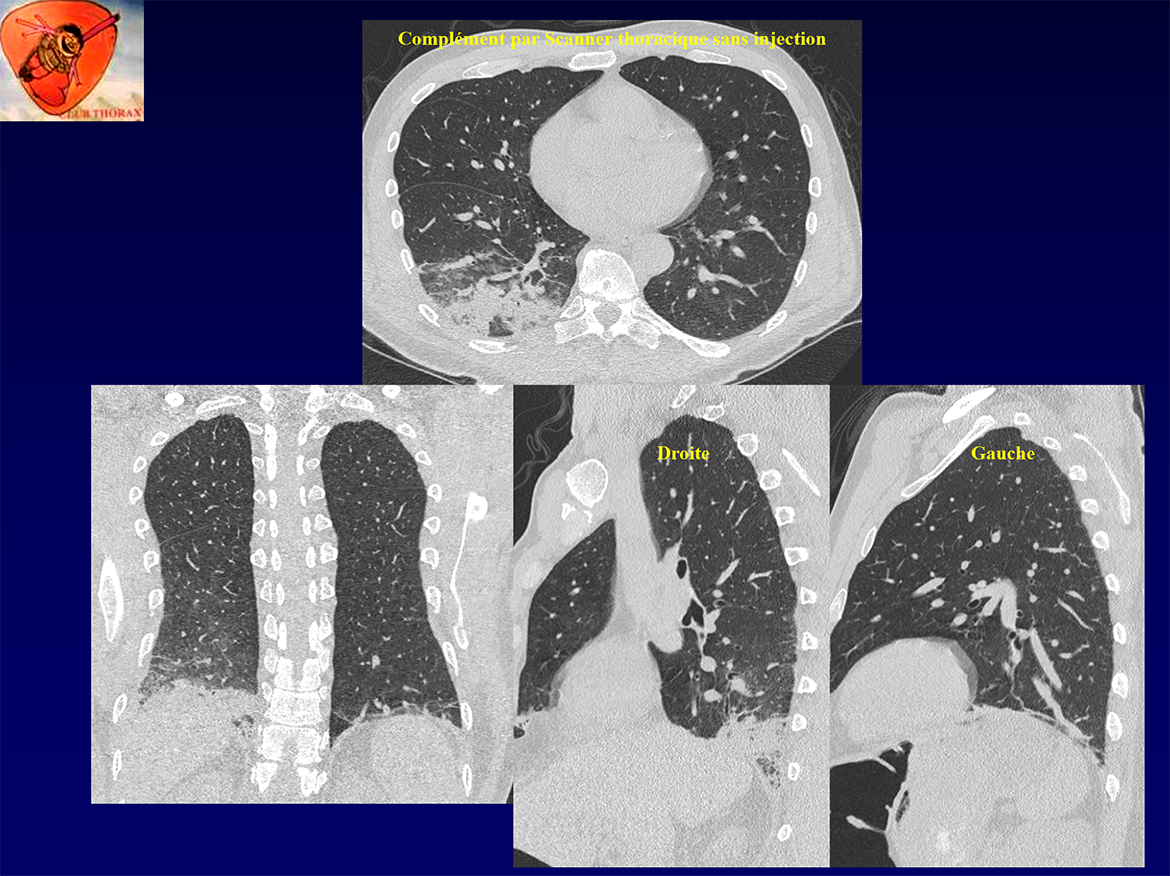

Homme, 59 ans.

Douleur lombaire droite hyperalgique.

Hyperleucocytose.

Suspicion de colique néphrétique ou de pyélonéphrite droite.

Scanner AP en urgence, qui innocente les reins, mais sur la base thoracique…